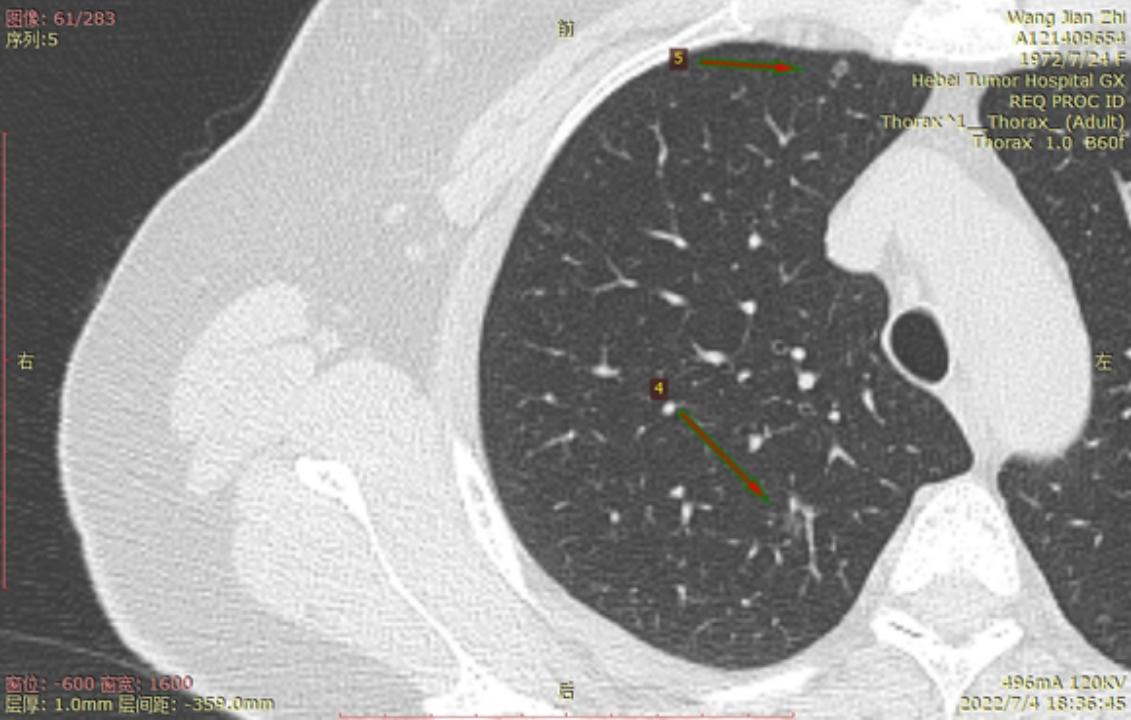

结4-5

右侧至少5枚以上的微浸润或原位腺癌,大的两枚结节微浸润,建议半年内把右侧5mm以上或者有危险的结节一网打尽。左侧结节还安全,安心随访